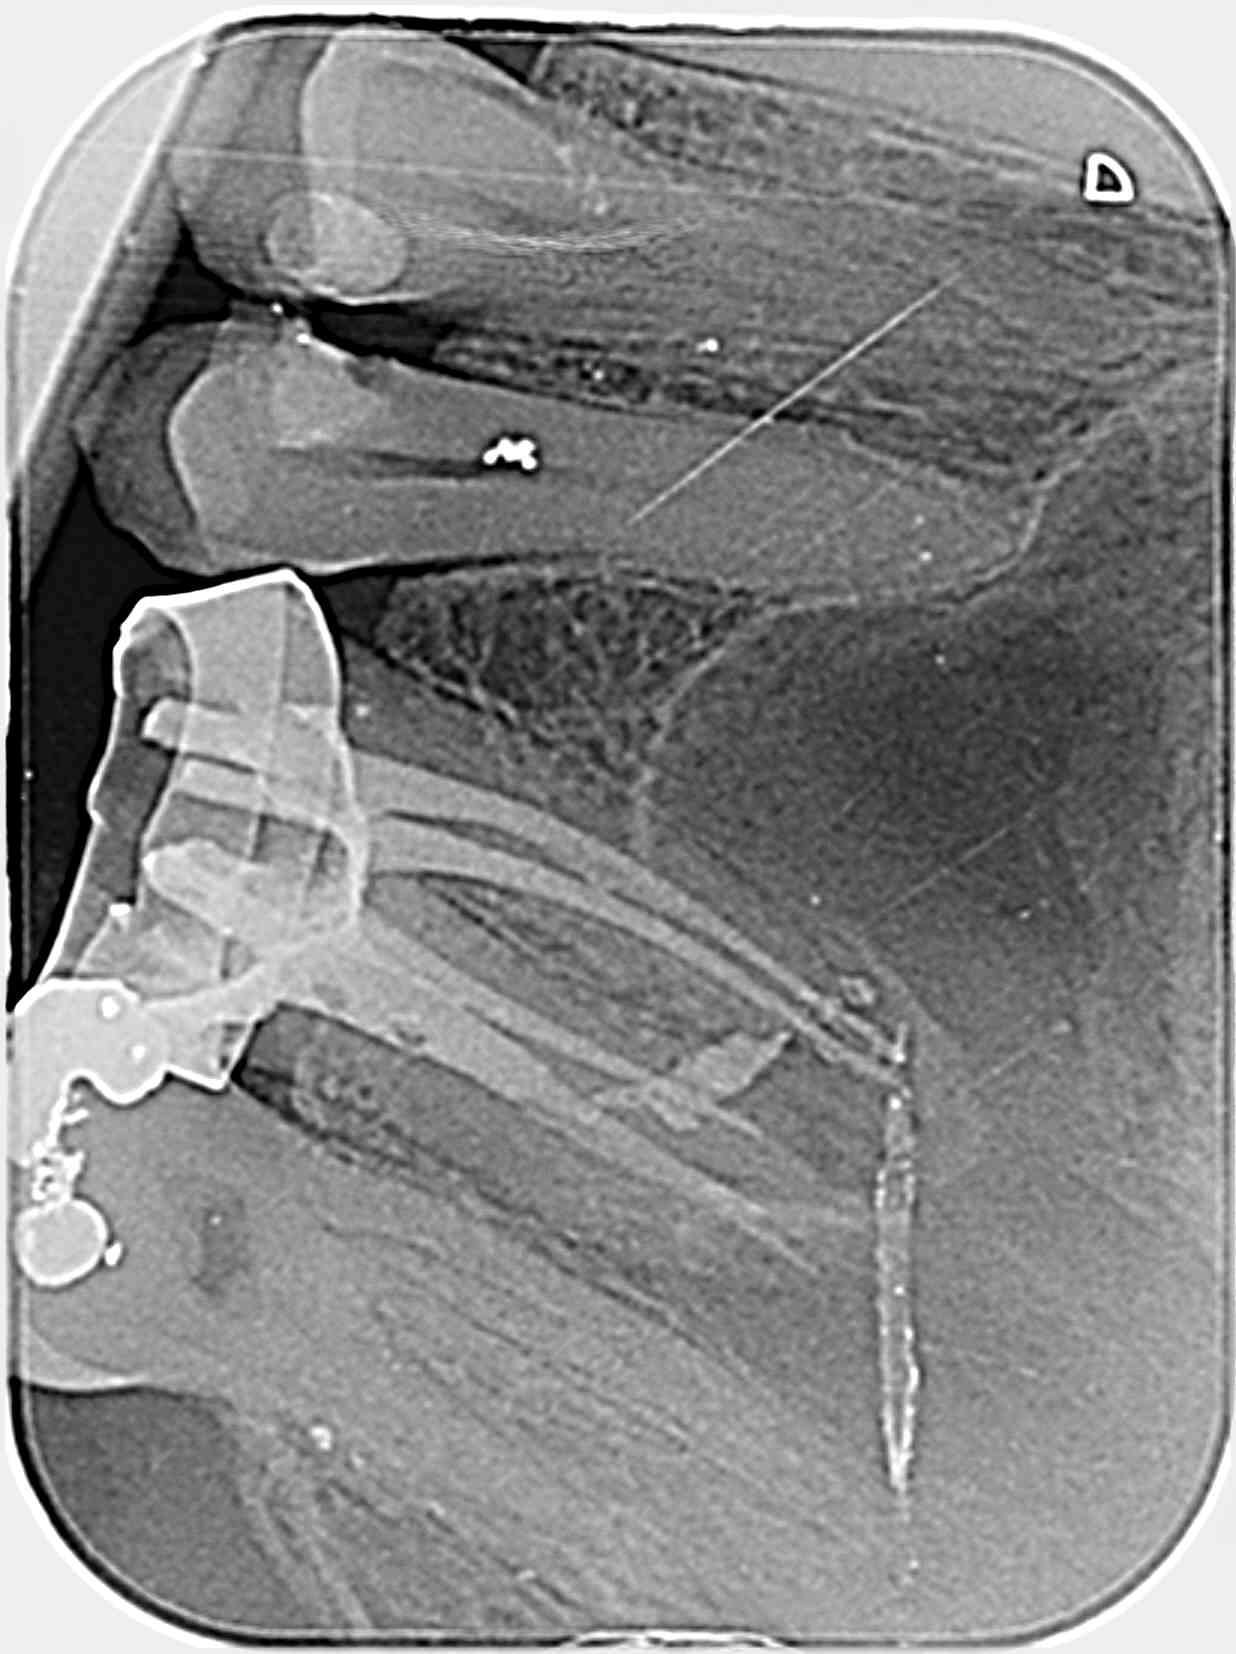

Reprise de traitement avec les Wam et reciproc.

Très convaincu avec les 20/07..

C11 vjtbl4 - Eugenol